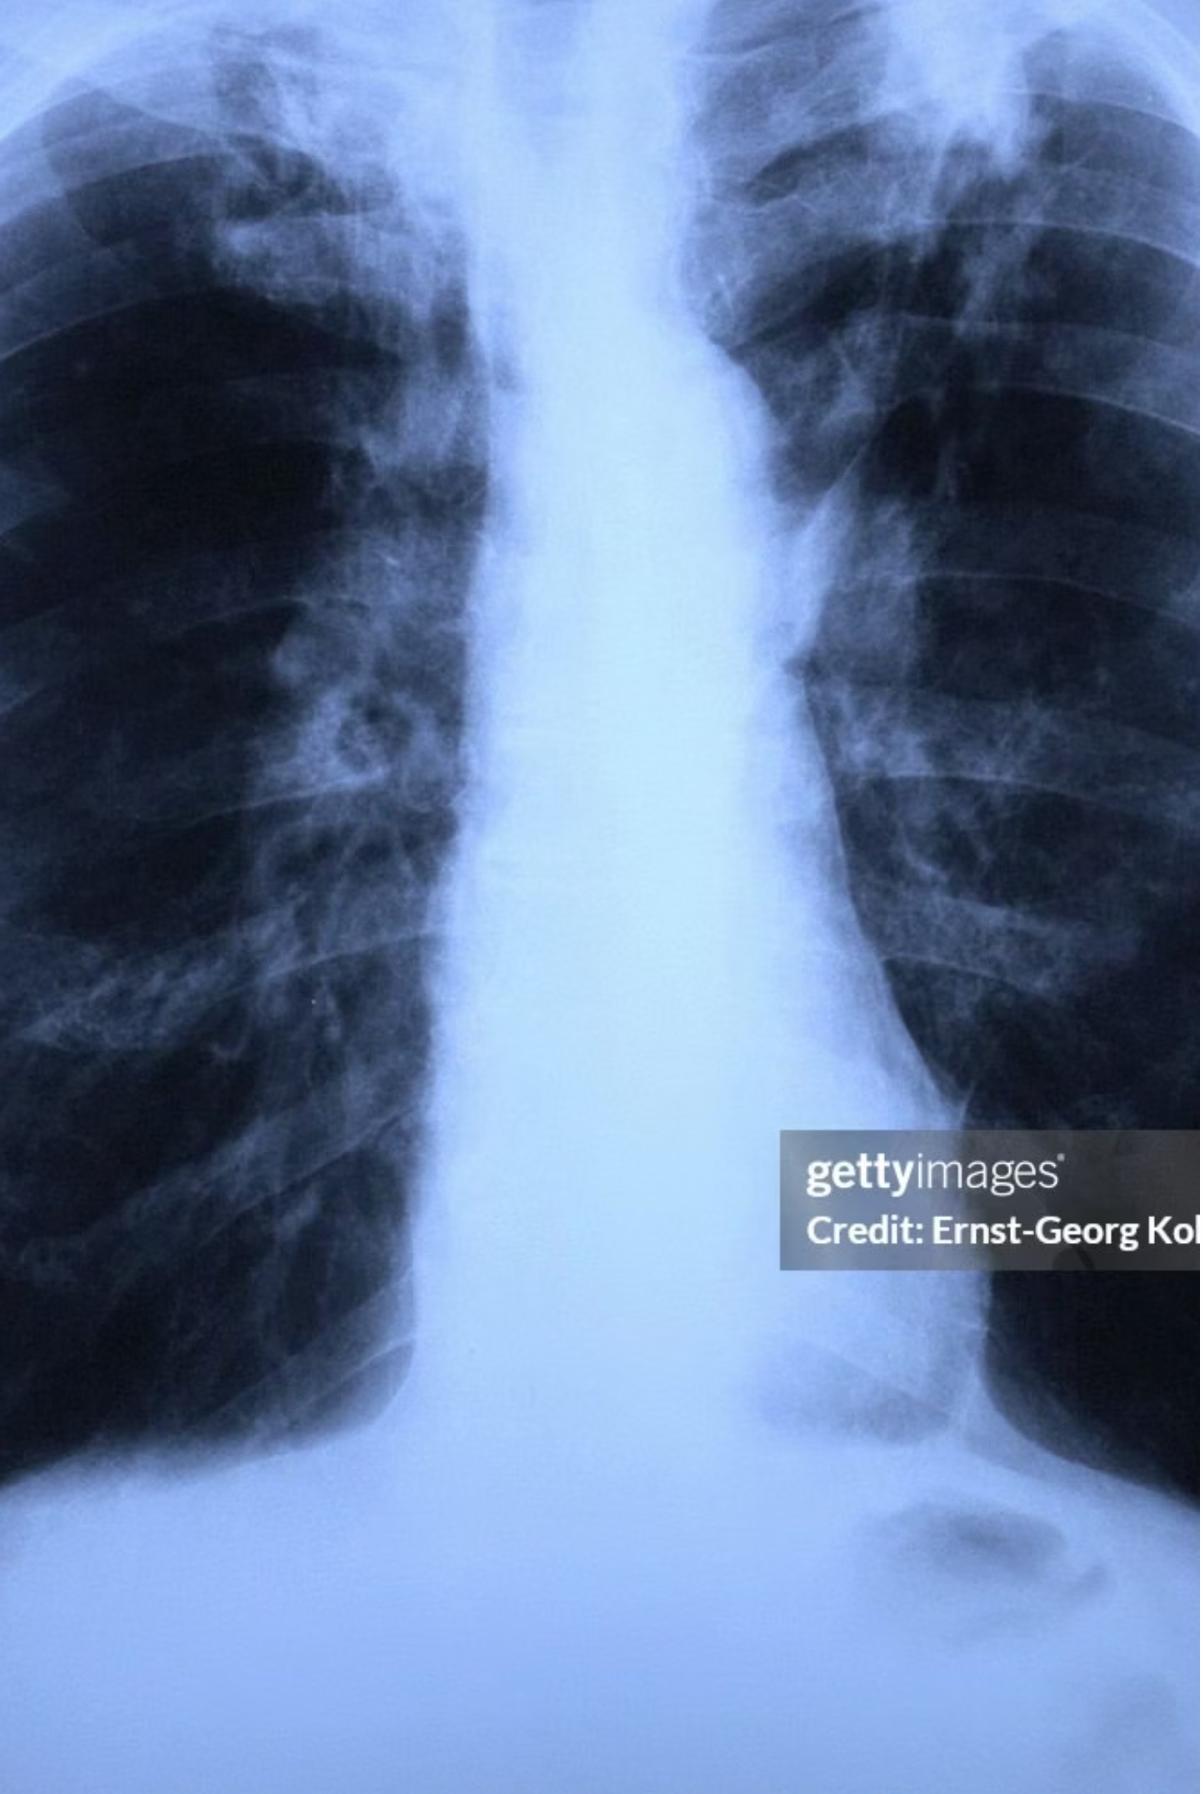

Reactivation Pulmonary Tuberculosis

Typically occurs in adolescents and adults.

1. Location Pattern

Usually confined to the apical segment of upper lobes or superior segments of lower lobes, representing secondary expansion of infection at previously seeded sites.

2. Clinical Features

- Lymphadenopathy: Little lymphadenopathy (distinguishes it from primary TB). -

- Cavitation: Associated with cavitation and endobronchial spread of bacilli.